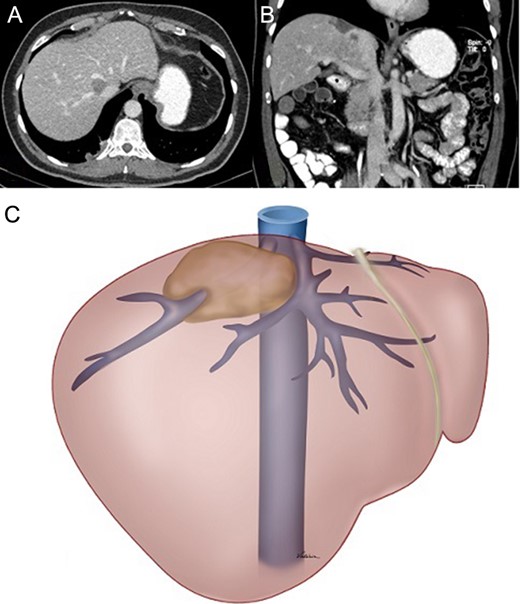

Double antiaggregant therapy was initiated on the second post-operative day with clopidogrel (75 mg orally daily) and aspirin (100 mg orally daily). One month after the procedure, clopidogrel was interrupted and aspirin maintained as single-antiplatelet therapy. Doppler US on post-operative Day 2 showed normal blood flow in the graft. Contrast-enhanced CT scans performed on post-operative Day 5 and 3 months after the procedure showed a properly positioned and patent graft (Fig. 6).

CT scan performed on the fifth post-operative day: (A) axial view, no intravenous contrast; (B) axial view, intravenous contrast inside the graft and (C) coronal view, graft filled with contrast.